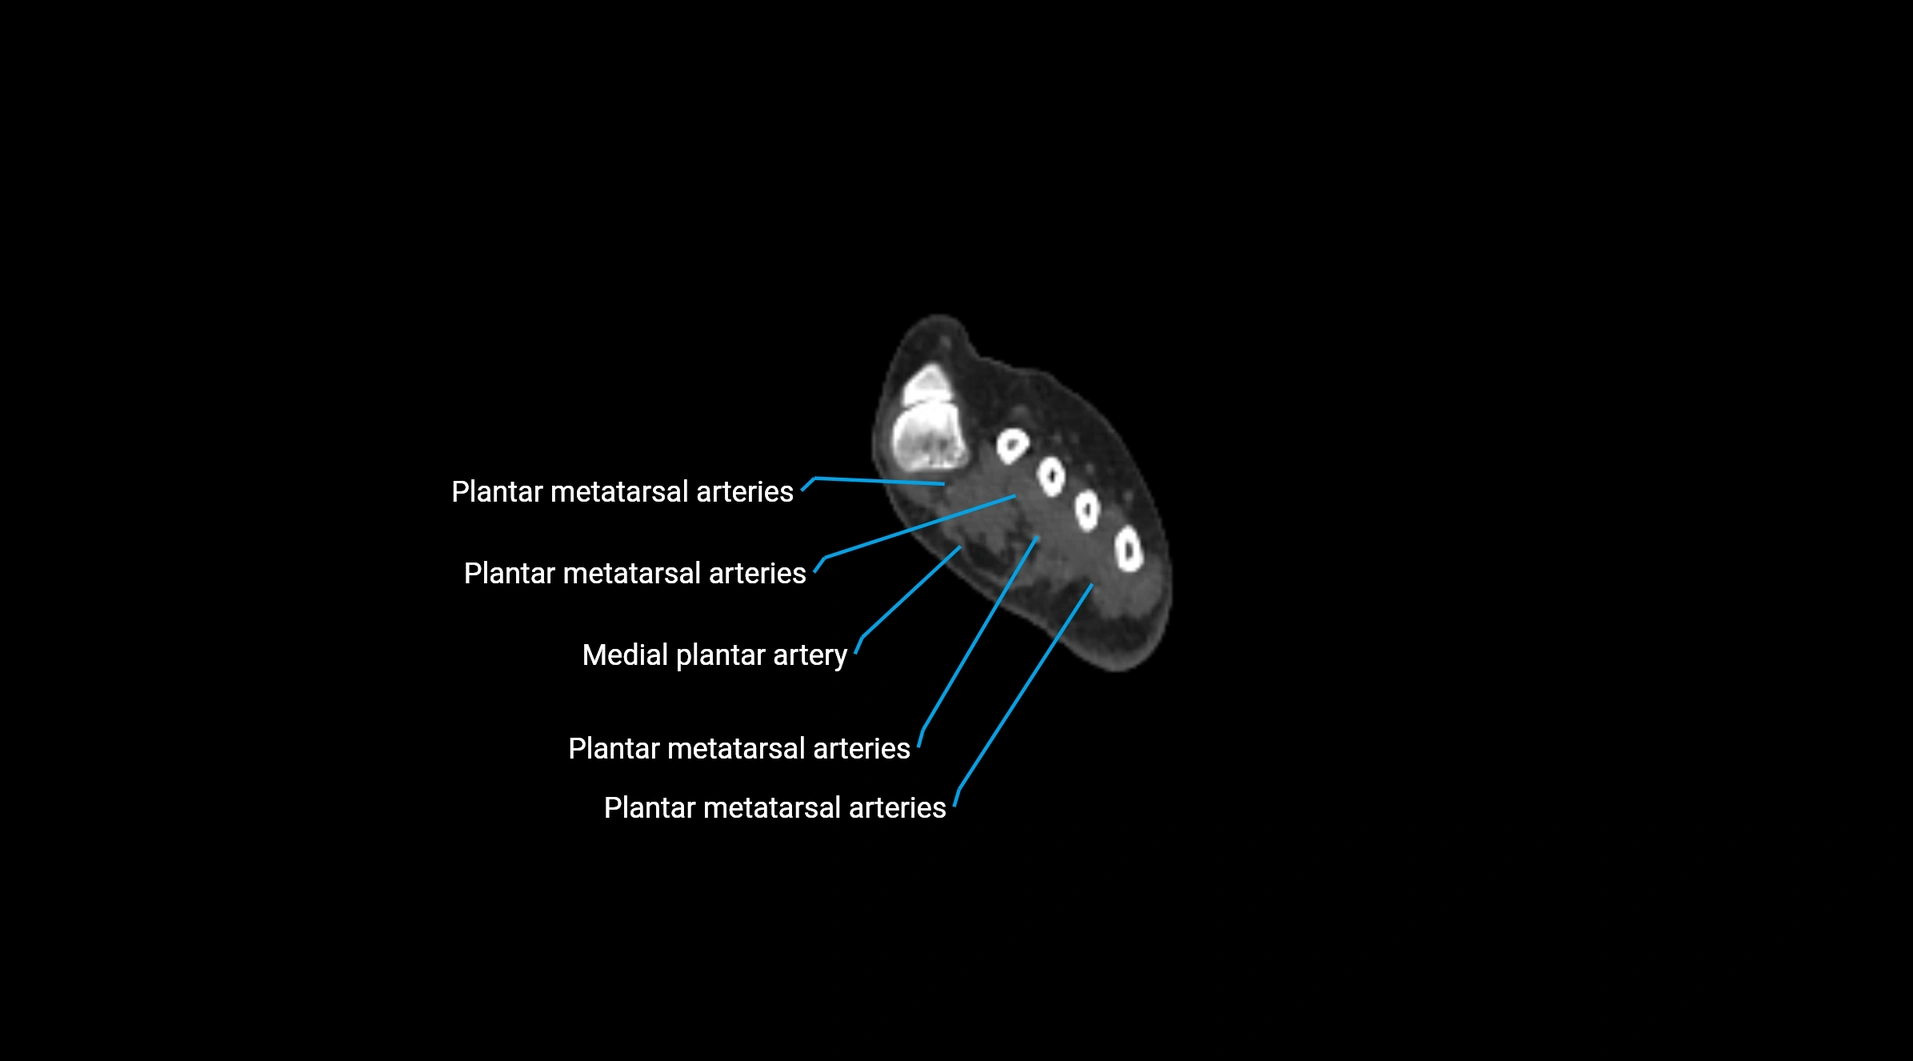

Contrast-enhanced CT (CTA):

• Gold standard for abdominal aortic imaging

• Provides excellent detail of lumen, wall, aneurysm, thrombus, and branch vessels

• Multiplanar and 3D reconstructions help in aneurysm measurement, stent graft planning, and dissection evaluation

• Detects acute rupture, traumatic injury, or occlusion with high sensitivity